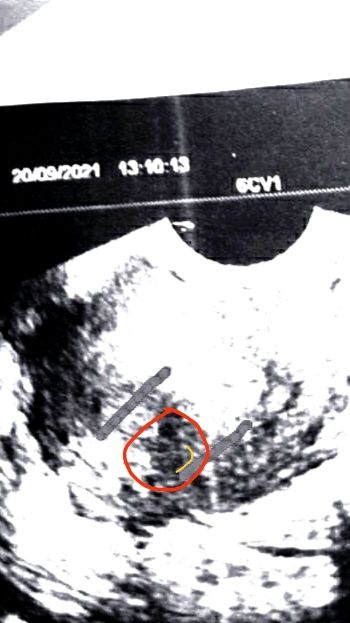

Ну так может и лицо, не понятно по фотке совсем ничего. Вы так все законтрастили, что не понятно где пя, где эмбрион. Саорее всего сосудистая сетка так на узи вышла, кажется каа будто лицо

Ну похоже, да. Но это получается уже недель 8-9 было?

Ну очень похоже на лицо. У меня с сыном когда в 10 недель врач узи делала и говорит: «ого, у вас уже мордашка такая!» Я посмотрела, на экране и правда эмбриончик с уже сформированным личиком (мне тогда показалось, что он на бабушку мою похож))))

Лена, по идее недель 7...

мария, 7 недель эмбриональных имею ввиду, 8-9 акушерских

Изображение Жёлтым обведён...